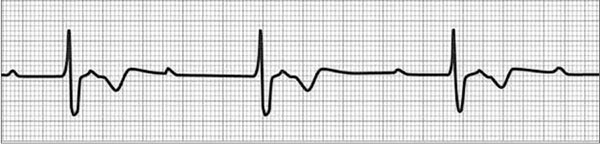

Block nhĩ thất cấp 1 (khoảng PR > 200 ms)

Hình ảnh điện tâm đồ blốc nhĩ thất cấp I

1. Blốc nhĩ thất cấp I

Là hiện tượng dẫn truyền chậm trễ từ tâm nhĩ xuống tâm thất, biểu hiện bằng đoạn PQ (PR) kéo dài trên điện tâm đồ > 0,20 giây. Hiện tượng này có thể gặp ở người bình thường hoặc trong một số bệnh lý của tim.

Biểu hiện trên điện tâm đồ Blốc nhĩ thất cấp I

- Khoảng PQ (PR) > 0,20 giây.

- Mỗi sóng P đều có một phức bộ QRS đi sau.

- Khoảng PQ (PR) thường dài từ 0,20 đến 0,40 giây.

- Đôi khi PR có thể dài tới 0,60 giây hoặc hơn làm cho nó có thể chồng lên sóng T của thất đồ.